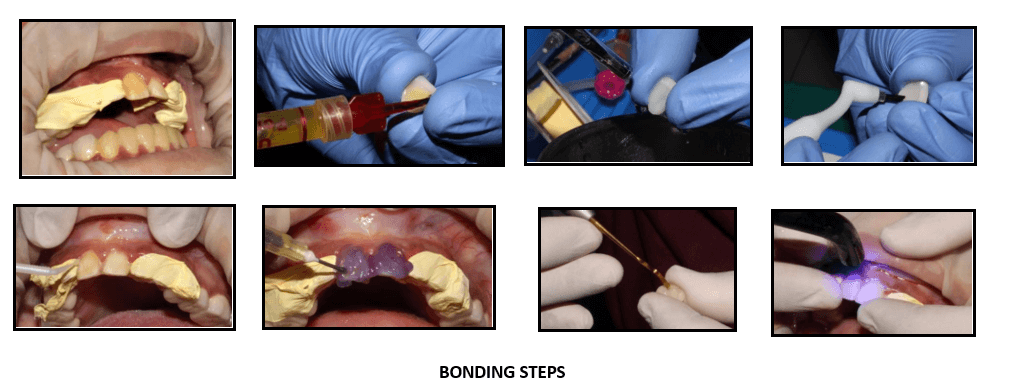

Calibra esthetic resin cement was used for the bonding of laminates.

Thoroughly clean all internal surfaces of the veneer with water spray and Etch the surface of the restoration with porcelain etch. Clean with water spray and dry.

Apply calibre silane to the Air dry the silanated surface of the restoration. Apply a single coat of Prime and bond NT adhesive to the internal surface of the veneer. Air dry for 5 sec. Light cure adhesive for 10 sec

Apply Prime & bond adhesive to tooth surface. The surface should remain wet for 20 sec. Gently air dry for 5 sec. light cure adhesive for 10

Dispense the desired calibra veneer Apply it on the veneer. Protect cement from exposure to light.

Seat the Tack the restoration in place by briefly light curing the gingival portion only for no more than 10 seconds. Remove excess cement.

Light cure all marginal areas for 20 seconds from each direction – buccal, lingual and interproximal

Removal of excess cement flash and finishing of the margins if